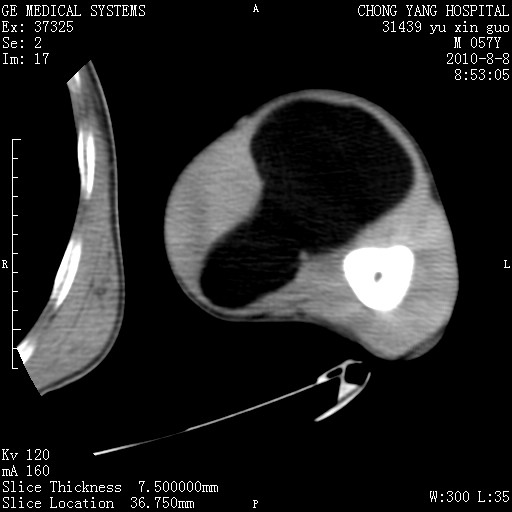

标题: CT28267:M57Y 上臂包块8年余。 [打印本页]

标题: CT28267:M57Y 上臂包块8年余。

典型脂肪瘤改变

上臂软组织内脂肪瘤。

包膜光滑、完整的脂肪密度肿块,支持脂肪瘤。